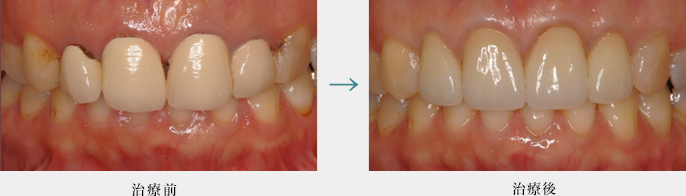

セラミック修復

セラミック修復は歯科技工士により製作されたセラミック素材のかぶせ物や詰め物による治療です。

生体に優しい材質で、審審美性の高い結果を得ることができます。

歯茎の形を整える手術

外科的に歯ぐきのラインのバランスを審美的に整えたのち、セラミックにて修復しています。